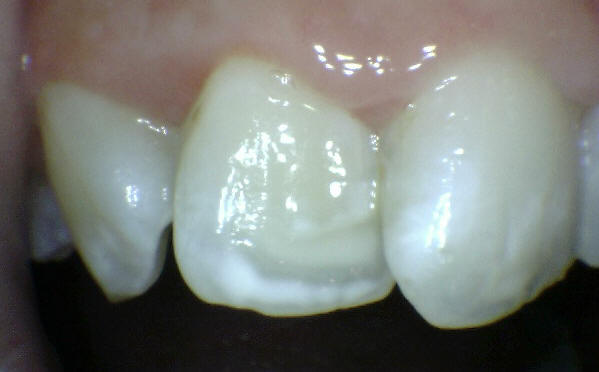

Imagen digital que representa la microfiltración y penetración del sellante realizado.

Microfotografía: Muestra como el sellador obtura la caries subyascente, evitando su avance.

Código 3 (Caries moderada) in vitro. Los códigos 3 in vivo debe ser sellado para evitar el avance del proceso carioso. (MNO)

Código 4 (Caries moderada) in vitro. Los códigos 4 in vivo deben ser tratados en forma operatoria con preservación dental (MOPD), porque presentan dentina infectada.